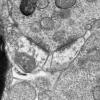

Neuroaxonal dystrophy (3)